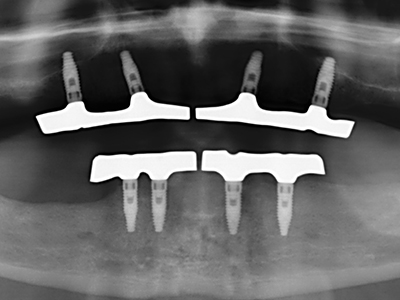

For removal of an implant, a vestibular bone cover that is replaced after removal of the implant screw can be prepared to retain the contour of the alveolar ridge.

There are additional applications in sinus surgery. Pathologies and foreign bodies can be removed from the sinus after concentric preparation of a generally trapezoid bone cover in the facial sinus wall. The bone cover is repositioned on conclusion of the intra-antral operation component and secured by wedging or adaptive sutures to prevent dislocation.